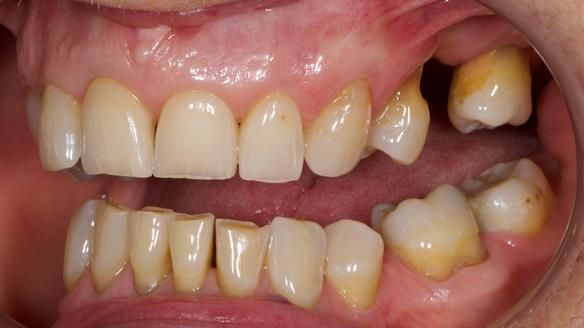

Welcome to Newsletter 61. In this edition, I walk through the process of creating and fitting a metal based lower partial denture for Joyce, a fit and healthy 76 -year-old woman.This issue shows the complete protocol workflow for achieving an exceptionally well-fitted and aesthetically good RPD.

Joyce's Case Presentation 61

Welcome to Newsletter 61. In this edition, I walk through the process of creating and fitting a metal based lower partial denture for Joyce, a fit and healthy 76 -year-old woman.

Joyce self-referred to me for specialist prosthodontics.

“Lower right side teeth now all gone. They didn’t fill them back in 1958 – just pulled them”

The missing lower right teeth to be replaced with a metal based partial denture.

The detailed clinical situation and treatment process are outlined below, with clinical work provided by me and technical work by Rowan Garstang. The treatment spanned six visits for denture fitting and one review.